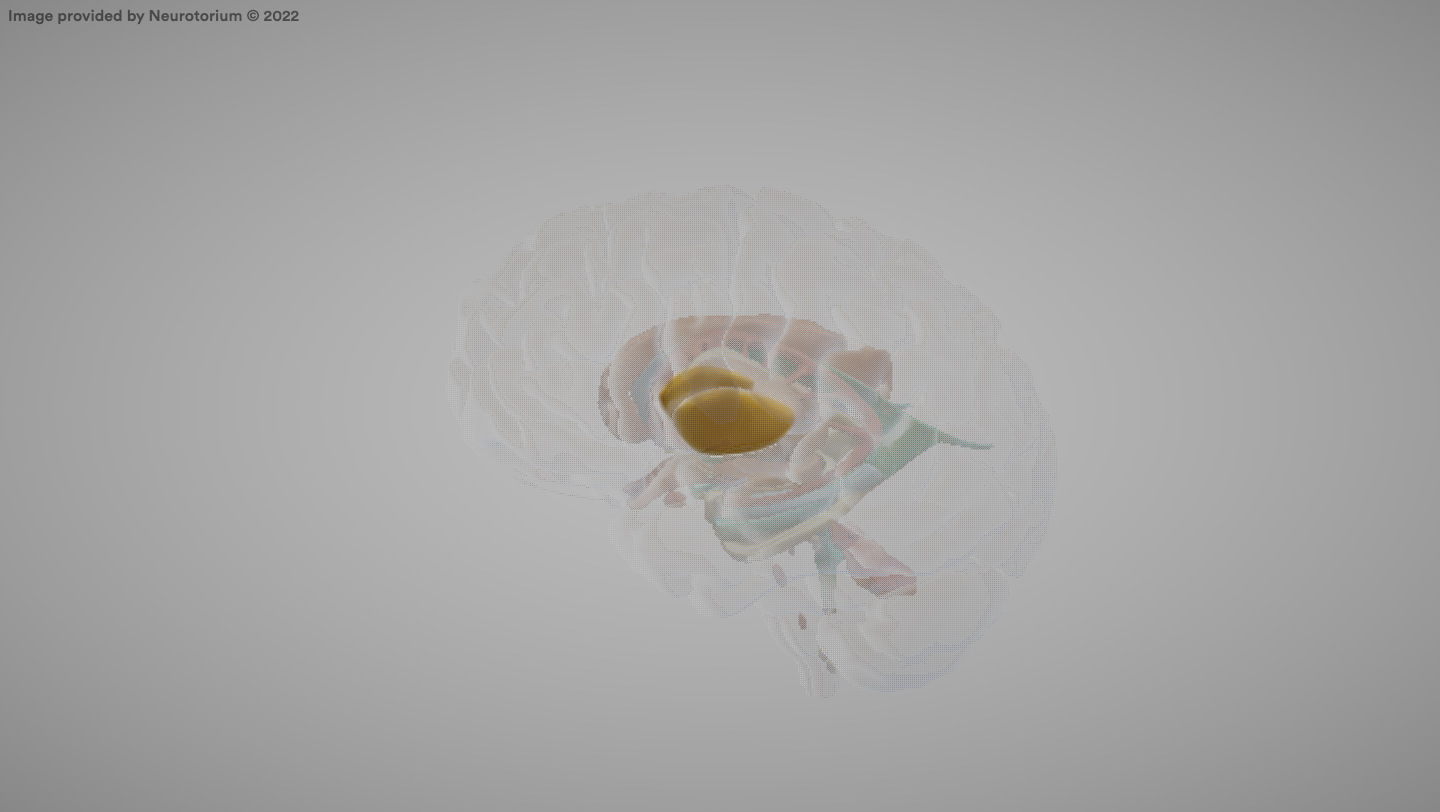

Amygdala

A brain structure involved in emotional processing, especially fear and aggression.

Thalamus

A brain structure that relays sensory and motor information to the cerebral cortex.